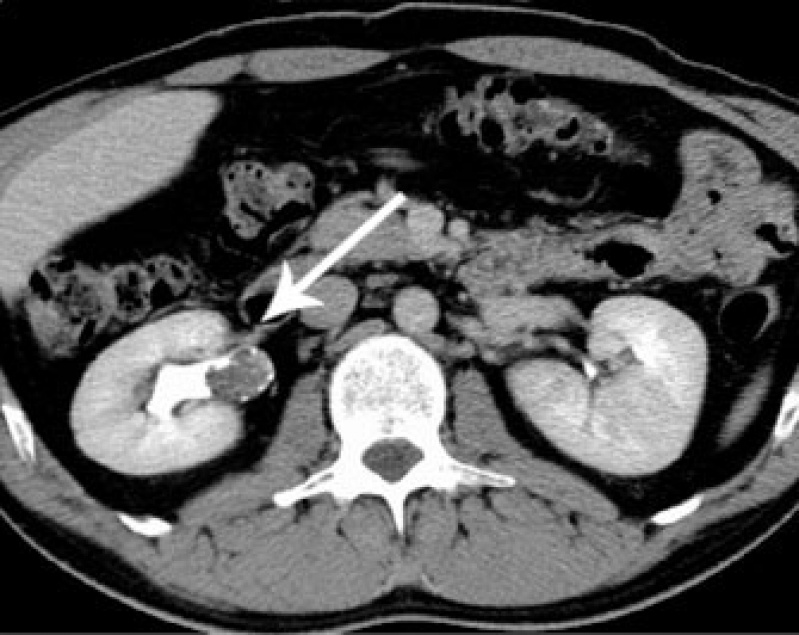

Exame de Imagem de Tomografia do Abdome Total

Medicom ExamesCom um exame de imagem é possível o médico analisar e ver o interior do corpo do paciente, para que desta maneira seja possível dar um diagnóstico para o paciente. O exame de imagem é diferente de...

Exame de Imagem de Tomografia do Abdome Total

Exame de Imagem de Tomografia do Abdome Total

Exame de Imagem de Tomografia do Abdome Total

Medicom ExamesCom um exame de imagem é possível o médico analisar e ver o interior do corpo do paciente, para que desta maneira seja possível dar um diagnóstico... Cotar Agora Saiba Mais